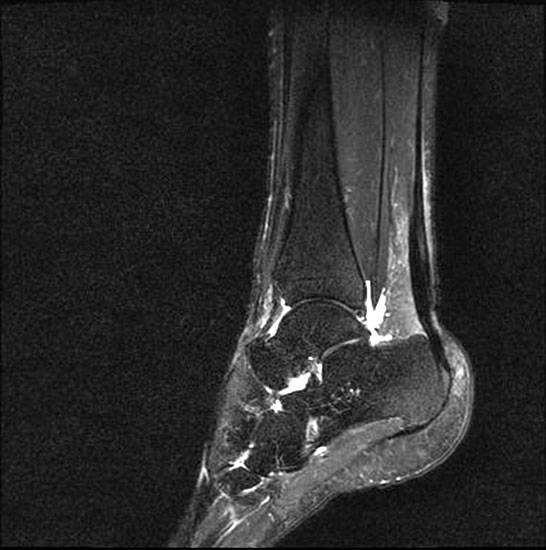

Stoßwellentherapie bei osteochondralen Läsionen

Die Osteochondrosis dissecans tali (OD) ist definiert als lokalisierte Pathologie der Gelenkfläche des Talus, die zur Abtrennung eines kartilaginären Fragmentes und subchondralen Knochens führen kann 93. Es existieren am Körper 3 Prädilektionsstellen für die Entwicklung einer OD mit unterschiedlicher Häufigkeit: Femurkondylen 75%, Talus 12% und Capitulum humeri 12%, sowie sonstigen Lokalisationen 1%. Abhängig vom Zeitpunkt des Auftretens unterscheidet man die juvenile Form (offene Wachstumsfuge) von der adulten Form (geschlossene Wachstumsfuge) (Dotti 2002).

Nach Dotti sind am Talus vorrangig die posteromediale und die anterolaterale Talusschulter betroffen. Die Ätiologie der OD an der anterolateralen Talusschulter scheint vermehrt traumatisch/repetitiv mikrotraumatisch zu sein, die der posteromedialen Talusschulter vermehrt idiopathisch.

Die Stadieneinteilung nach Berndt und Harty umfasst 4 Stadien und ist unabhängig von der Lokalisation der OD anwendbar 94.

Die Stadieneinteilung nach ARCO (Association Internationale de Recherche sur la Circulation Osseuse) berücksichtigt die Kombination aus MRI-Zeichen, Nativradiologie und Knochenszintigraphie 95.

Als Alternative zu operativen Maßnahmen wird bei frühen Stadien der OD auch der Einsatz fokussierter Stoßwellentherapie diskutiert, wenngleich es bislang wenig klinische Studien zur ESWT bei OD am Talus gibt.

Die ESWT wird in der Regel in einer Sitzung unter Leitungs– oder Allgemeinanästhesie durchgeführt, wobei nach Empfehlungen der DIGEST eine mittlere Energieflussdichte von 0,35mJ/mm² und eine Anzahl von 2500 Impulsen empfohlen wird. Bei hochenergetischer Behandlung (>0,5mJ/mm²) kann eine Schädigung des Knorpels nicht sicher ausgeschlossen werden 97.

Nach der Behandlung wird eine Entlastung für ca. 2 - 6 Wochen empfohlen. MRT-Kontrollen sind nach 3, 6 und 12 Monaten sinnvoll.

Aufgrund der Datenlage kann die Anwendung der ESWT bei osteochondralen Läsionen des Talus in frühen Stadien (1 und 2 nach ARCO) erwogen werden. Für eine Therapieempfehlung sind allerdings weitere Studien, insbesondere zur Therapie der OD des Talus zwingend erforderlich. Aufgrund der technischen Schwierigkeit der Behandlung bei teilweise schlechter Erreichbarkeit der Läsion, sollte diese Indikation erfahrenen Anwendern vorbehalten bleiben.